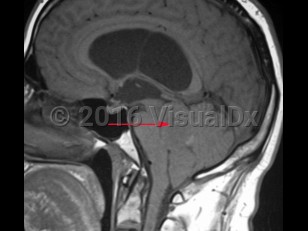

An ependymoma is a tumor of the brain or spinal cord arising from ependymal cells. Ependymomas account for 4% of central nervous system (CNS) tumors in adults and 10% of CNS tumors in children. In children, they are most often located in the 4th ventricle and posterior fossa, whereas in adults, they are more frequently located in the spinal cord. In the spinal cord, they tend to occur centrally, causing symmetric cord expansion. Peak incidence in adults occurs between 30 and 40 years of age.

Signs and symptoms depend on tumor location but may include headache, vomiting, papilledema, lethargy, ataxia, nystagmus, weakness or difficultly walking, sensory disturbance, urinary or bowel dysfunction. Ependymomas have a high incidence in patients with neurofibromatosis type 2.